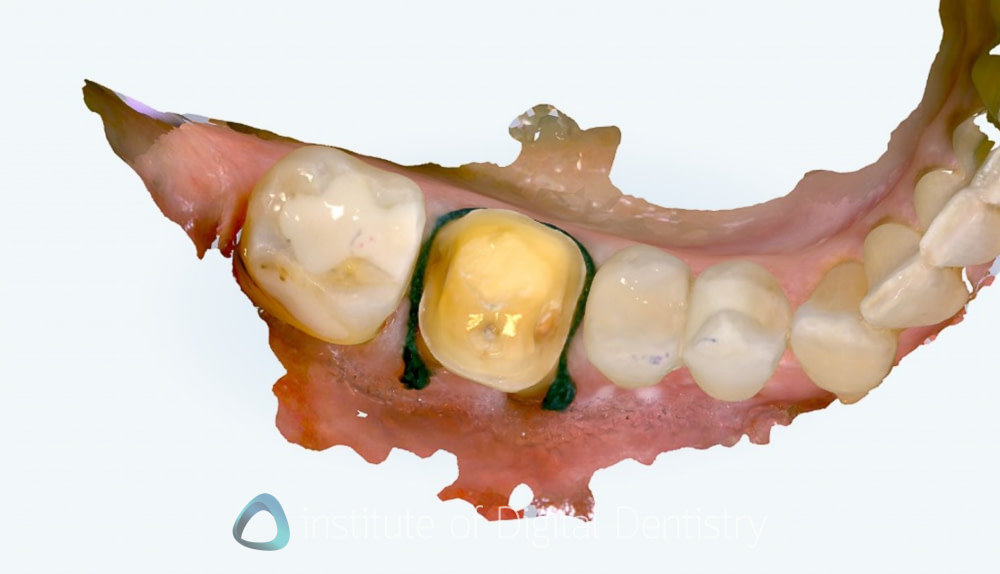

Beyond dimensional accuracy, my favorite part of the Lumina is the scan textures and quality. It produces exceptional final scans. These are the nicest I have seen on the market.

The photorealistic textures are simply unmatched by any other scanner currently available in terms of detail, resolution, and colors. These visuals offer both clinical and communication advantages, and they work well within the extensive range of patient communication apps available within the Align Oral Health Suite.

These scan images really are nice to look at, even for patients. I mean, the detail capture is market-leading, with the scanning picking up even the twists on a ligature tie (see the images below). Gingival texture, tooth characteristics, and restoration details appear with clarity that approaches the quality of intraoral photography. It really is incredible tech.

Integrated Intraoral Camera: High-definition intraoral images are captured while scanning, and multi-angle views of each tooth can be seen. Clinical applications include displaying and tracking gingival health with realistic images.

The UI is very well done here; rather than showing you multiple images, it presents you with a magnifying glass that you can put on any tooth. Then the software shows you the NIRI images and intraoral images captured in that site.